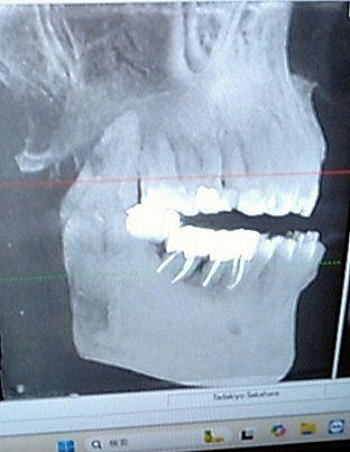

![]() 原始的記録媒体だって! (2025年6月6日早川歯科X線正面) |

![]() 骨だけになった仙人! (2025年6月6日早川歯科X線右側面) |